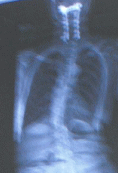

XX病院受診 EOSにて全身の様子を見てくださる 前と同じ状態との事で、頸椎も異常なしで、次は半年後 ![]() これが、EOSの画像です 首のボルト画像が、よくわかります 背中の画像で、圧迫骨折の為に、まるくなっているのも解ります ![]() こちらは、ちょと驚きです 背中の丸みが、身体の均衡迄崩しています 左肩が下がっているとか ちょっと見苦しい写真ですね 左側に足を崩す癖があったから、こうなったのかもしれません 一種の背骨湾曲症だそうです 足の方まで続くのですが、これ以上見苦しいのは、お見せ出来ないので切りました (注)EOSとは、一瞬にして、2方向同時に全身を撮ることができる 放射線量も低い放射線機器(この説明で良いと思いますが) |